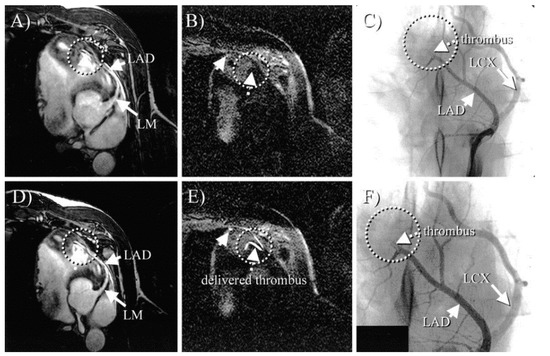

- Botnar, R.M.; Buecker, A.; Wiethoff, A.J.; Parsons, E.C.; Katoh, M.; Katsimaglis, G.; Weisskoff, R.M.; Lauffer, R.B.; Graham, P.B.; Gunther, R.W.; et al. In Vivo Magnetic Resonance Imaging of Coronary Thrombosis Using a Fibrin-Binding Molecular Magnetic Resonance Contrast Agent. Circulation 2004, 110, 1463–1466. [Google Scholar] [CrossRef] [PubMed]

- Spuentrup, E.; Botnar, R.M.; Wiethoff, A.J.; Ibrahim, T.; Kelle, S.; Katoh, M.; Özgun, M.; Nagel, E.; Vymazal, J.; Graham, P.B.; et al. MR imaging of thrombi using EP-2104R, a fibrin-specific contrast agent: Initial results in patients. Eur. Radiol. 2008, 18, 1995–2005. [Google Scholar] [CrossRef] [PubMed]

- Vymazal, J.; Spuentrup, E.; Cardenas-Molina, G.; Wiethoff, A.J.; Hartmann, M.G.; Caravan, P.; Parsons, E.C. Thrombus imaging with fibrin-specific gadolinium-based MR Contrast Agent EP-2104R Results of a Phase II Clinical Study of Feasibility. Investig. Radiol. 2009, 44, 697–704. [Google Scholar] [CrossRef] [PubMed]